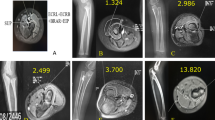

The origin of 34 FCRBs detected on the MR images examined was the distal third of the anterior surface of the radius. In addition, the insertion of FCRB was the second metacarpal bone in 82.4% (Fig. 3) and the os trapezium in 17.6% (Fig. 4). The distribution of FCRB insertions by sex is presented in Table 3.

Symptoms caused by FCRB are related to its location and function17,18,19. Radial-sided pain of the wrist, interosseous anterior compression, inflammation due to overuse of the muscle where it attaches to the radius, and FCRB tenosynovitis are some of the disorders that may occur19,20. In distal forearm surgeries, especially in the approach for distal radius fracture, the flexor carpi radialis (FCR) muscle is a location determinant because of its strong and thick structure, rare anatomical variations, and superficial palpability, and such operations are planned according to the FCR21,22 (Fig. 5). In addition to some symptoms that may be caused by an FCRB located close to the FCR, another important clinical aspect is related to distal radius fracture surgery with the standard approach site. In this type of operation, surgeons are more likely to encounter the FCRB due to its location1.